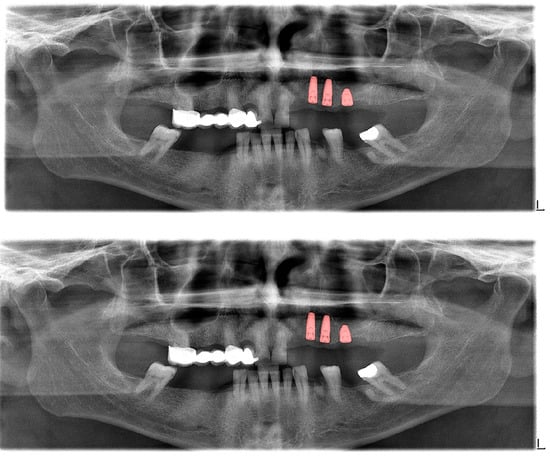

Figure 5.

Automatic segmentation of dental implants. Manual segmentation (upper image) and automatic segmentation (lower image) can be seen above.